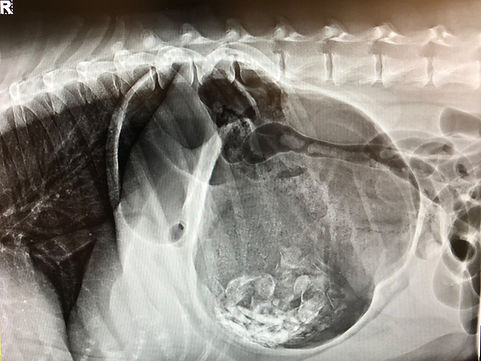

Unfortunately, a rare but regularly seen disease known as Gastric Dilatation and Volvulus (GDV) or “bloat and stomach flipping” is seen mostly in large breed dogs with deep chests like standard poodles, Great Danes, German Shepherds, Weimaraner, and Labrador Retrievers, etc.  This condition is invariably fatal and pets can very rapidly turn from completely normal to mortally ill in just a few hours.  Therefore, VIP recommends all affected breeds have a “prophylactic gastropexy” procedure performed during your pet’s spay/neuter procedure or anytime if your pet has already been spayed or neutered or is not being spayed or neutered.

During this procedure, Dr. Jones delicately attaches the stomach to the body wall with sutures and this attachment eventually forms a scar, greatly reducing the chances your pet’s stomach FLIPS during a bloating incident.  This procedure does not prevent bloating, just volvulus (flipping) which is the most dangerous part of the disease process in the short term.

This procedure and the scar that has formed, has been known to very rarely fail, resulting in full GDV episodes.  However, this procedure is still highly recommended and extremely effective at preventing life-threatening GDV episodes.